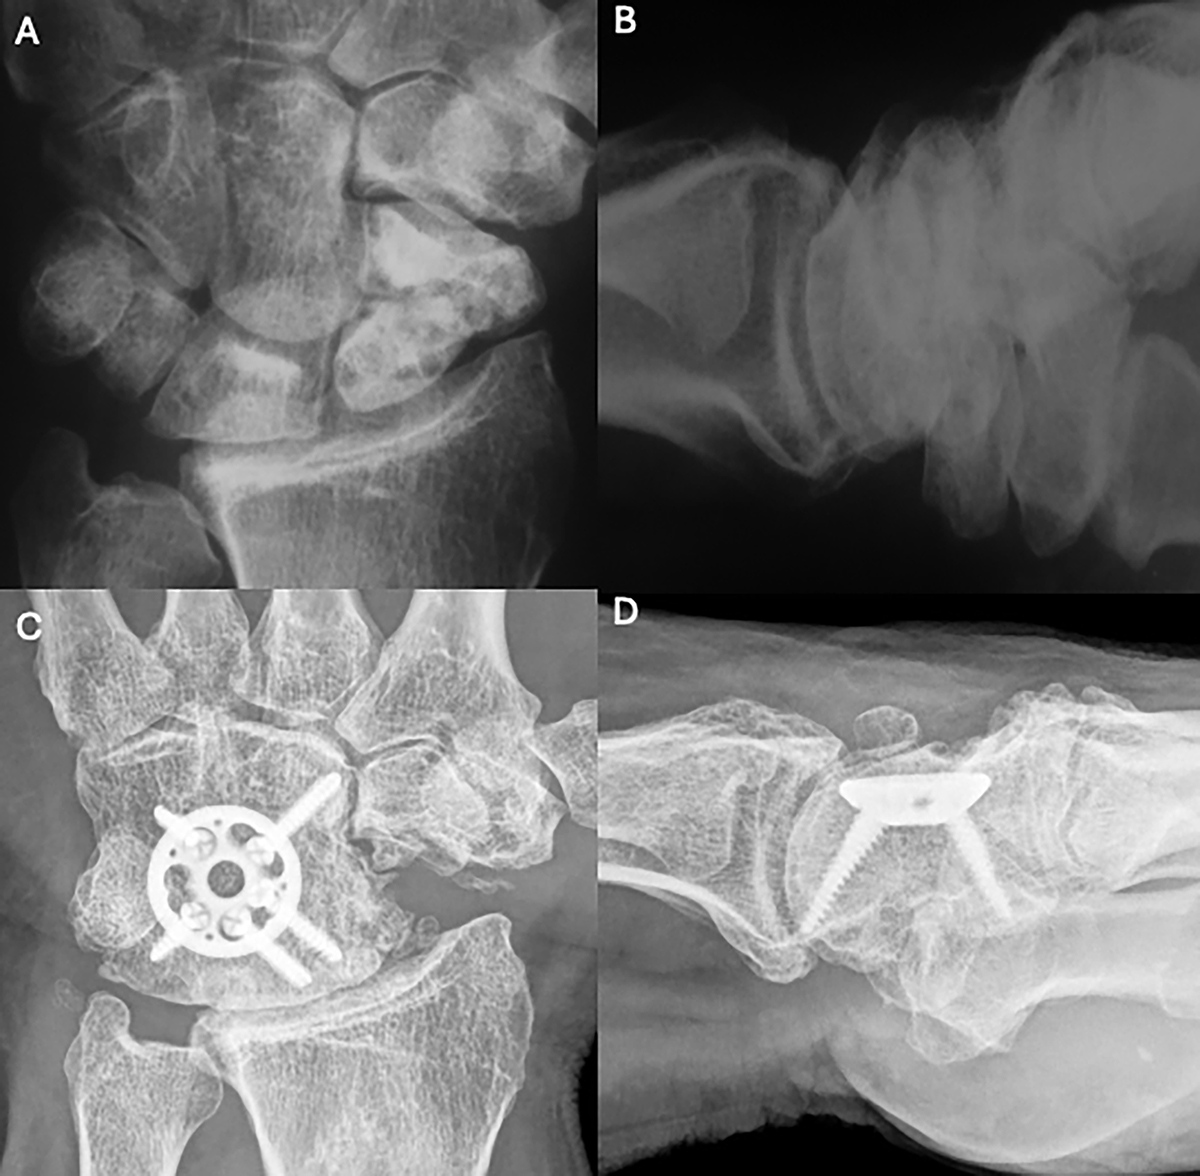

Figure 7

Clinical case of 4-Corner Fusion. A and B. Preoperative wrist X-rays of SNAC stage II (AP and Lateral views). C and D. Postoperative wrist X-rays (AP and Lateral views) after 17 years. Source: Dr. Emmanouil Apergis.